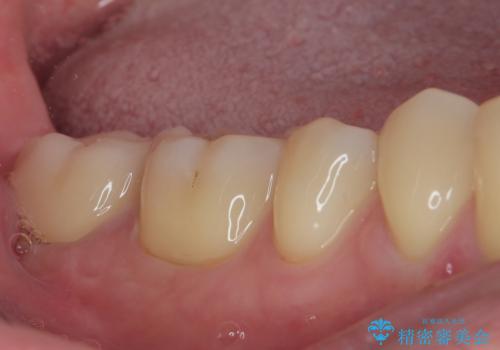

その後は速やかに根管治療を行い、初回の処置以降は痛みや違和感が一気に引いたため、根管治療後にオールセラミッククラウンにて補綴治療を行うこととしました。

治療後は一切痛みや違和感を感じることなく、快適に過ごすことができています。

診断には苦労しましたが、誤った処置を行うことなく、無事に治療を終えることができました。